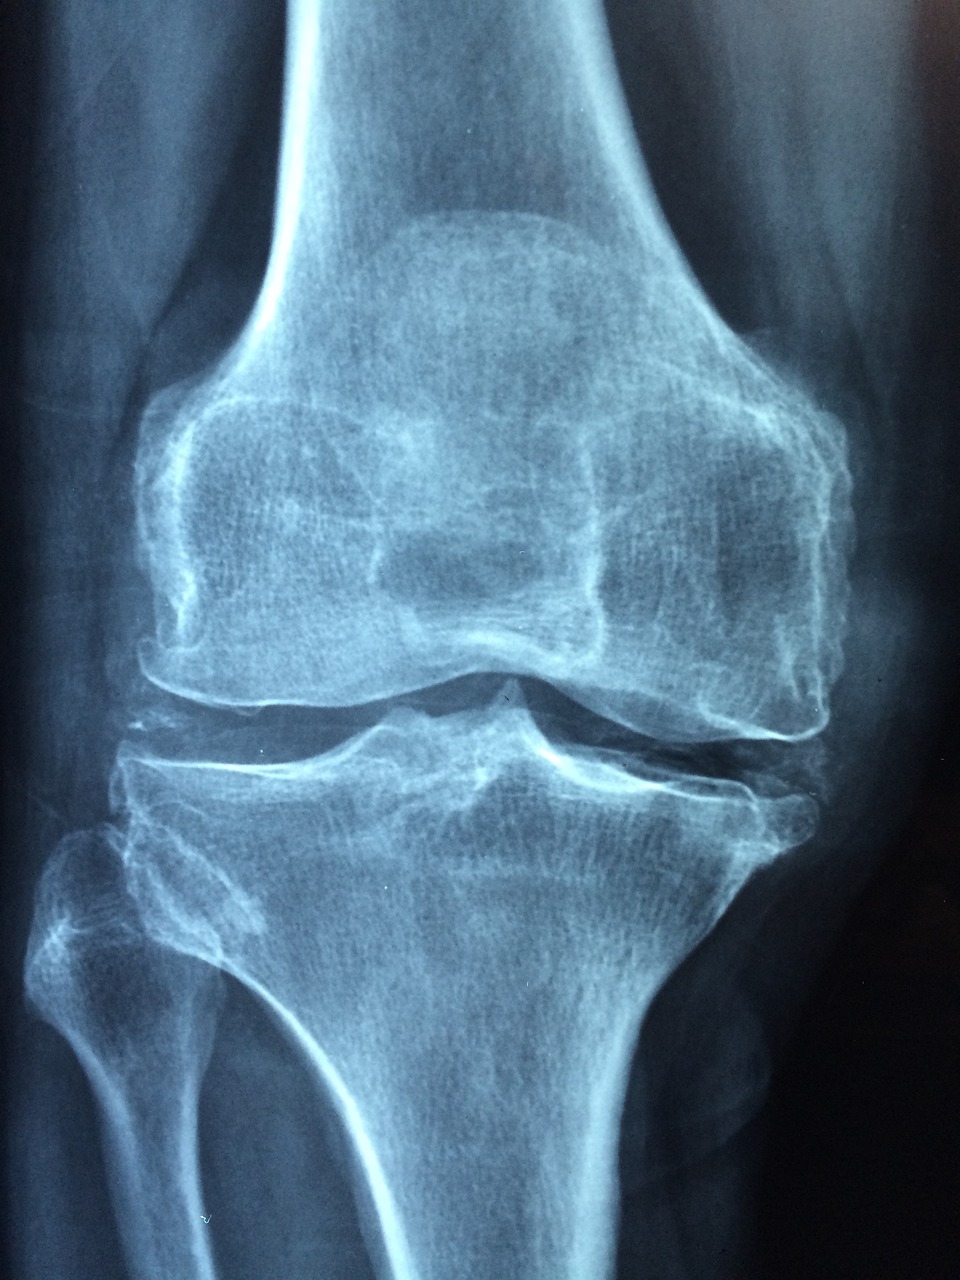

Objawy obiektywne uszkodzenia: Tkliwość nad zajętym obszarem, wysięk i trzeszczenie lub uczucie ‘chwytania’ mogą być obecne podczas szerokiego zakresu ruchów. Zwykłe zdjęcie rentgenowskie i rezonans magnetyczny nie zawsze mogą wykazać uszkodzenie chrząstki stawowej.

uszkodzenia chrząstki

Uszkodzenie chrząstki kłykcia przyśrodkowego kości udowej uwidocznione podczas artroskopii (po lewej) i podczas operacji z dostępu otwartego (po prawej).